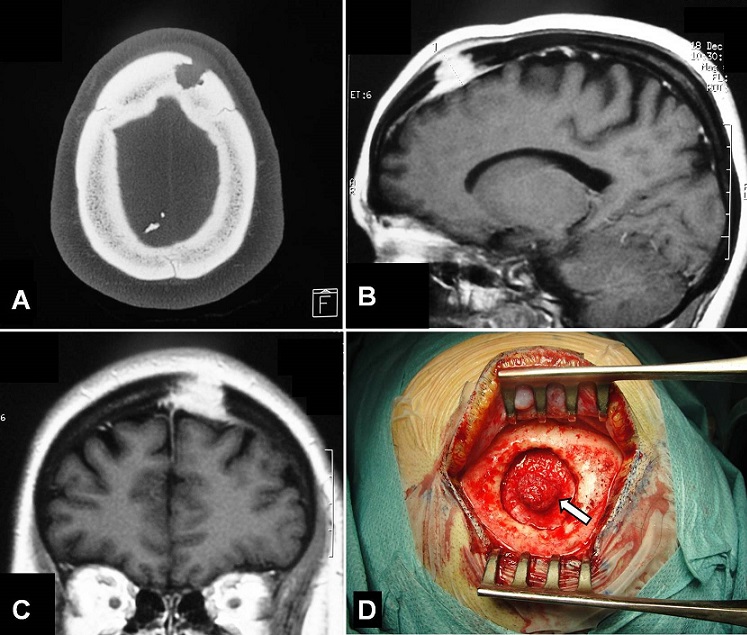

A 37-year-old woman, previously healthy with no history of trauma, presented with a scalp swelling of the left frontal region. The swelling was present for the last one year and had gradually increased in size with recent localized headache. The patient had no neurologic deficit. Local examination showed a painful local swelling of about 25 mm in diameter in the left frontal area and appeared to arise from the bone. Hematological and biochemical investigation results were within the normal range. Computed tomography scan revealed a left frontal intradiploic mass with bone defect (figure A). Magnetic resonance imaging showed that the lesion was soft with homogeneous enhancement following gadolinium injection. There was erosion of both inner and outer table of the cranial vault with extracranial and intracranial extradural extension (figures B and C). The tumor was excised completely and the surrounding bone was removed (figure D), followed by cranial reconstruction. There was no intradural extension of the lesion. Histologically, the tumor was diagnosed as meningothelial meningioma. The patient has been well for 1 year following the operation with no evidence of recurrence. Meninigiomas are primary tumors of arachnoid cell layers and the lesions are in purely settled intradural locations. Meningiomas in extradural locations are very rare and should be considered in the differential diagnosis of osteolytic skull vault lesions.